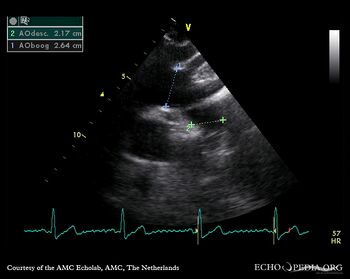

E00552.jpg

PLAX: dilated aortic root PLAX: 2-D measurement of aortic root